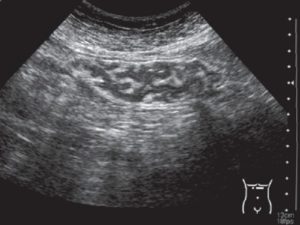

Здоровая прямая кишка на УЗИ выглядит округлым, немного вытянутым органом с ободком, отходящим от мышечного слоя. Ультразвуком его сканируют в поперечном и продольном срезах.

В норме в кишечнике отсутствуют все перечисленные «находки». Показатели трансабдоминального УЗИ находятся в пределах:

| Терминальный отдел | 5 см |

| Средний отдел | 6 – 10 см |

| Среднеампулярный отдел | 11 – 15 см |

| Толщина стенки | Более 9 мм |

| Просвет кишки | Визуализируется, без расширений и сужений |

| Количество слоев кишечной стенки | 2 |

| Наружные контуры стенок | Ровные |

| Регионарные лимфоузлы | Не определяются |